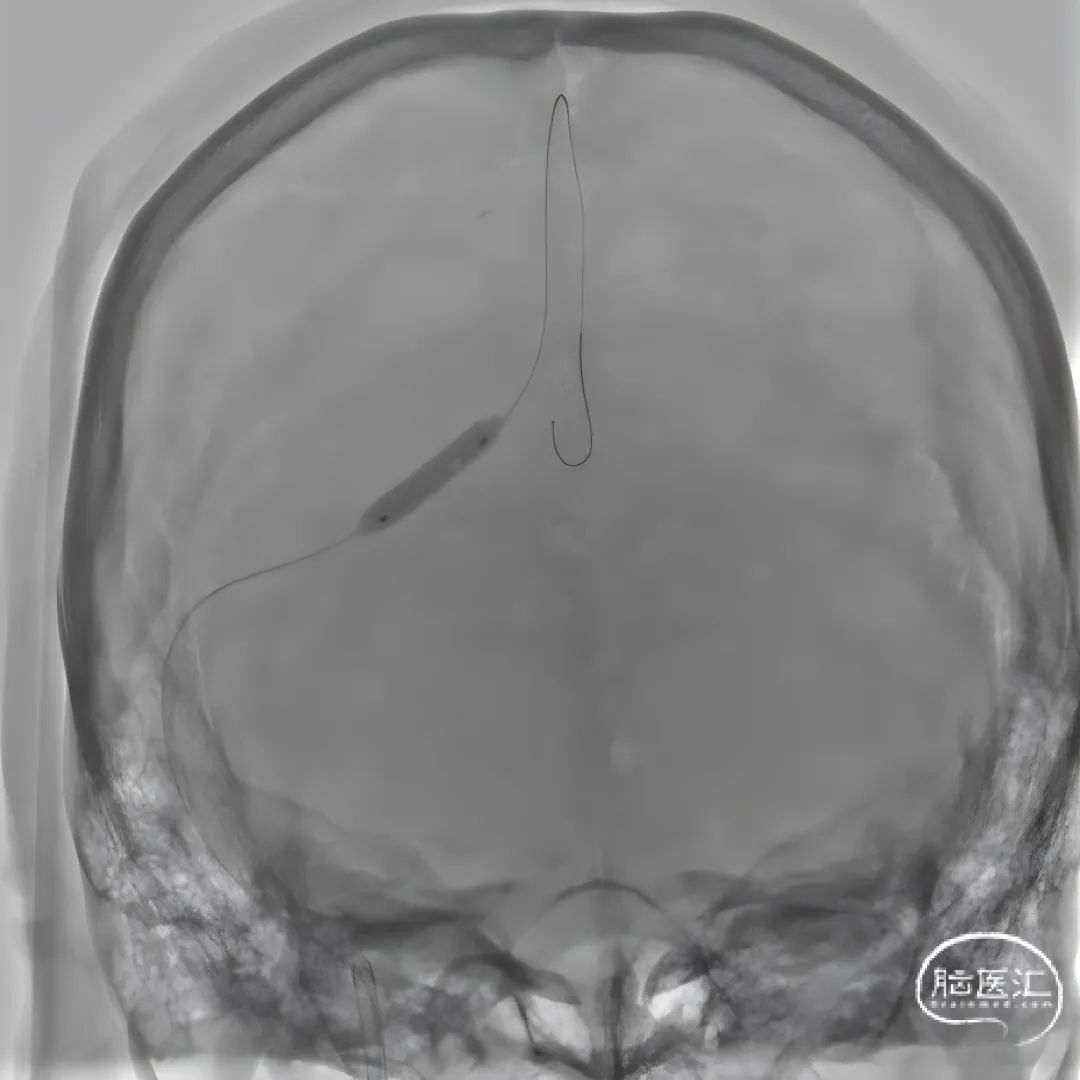

使用5F动脉鞘和8F静脉鞘,8F导引导管,300cm微导丝,Rebar™ 27微导管,4*15mm球囊。

再次给予球囊扩张,球扩后复查造影。

留置微导管以6ml/h尿激酶(1万U/ml)持续泵入。

第二次术后次日复查头CT,置管溶栓3天后(4月6日)拔除微导管及静脉鞘,复查头颅MRV。